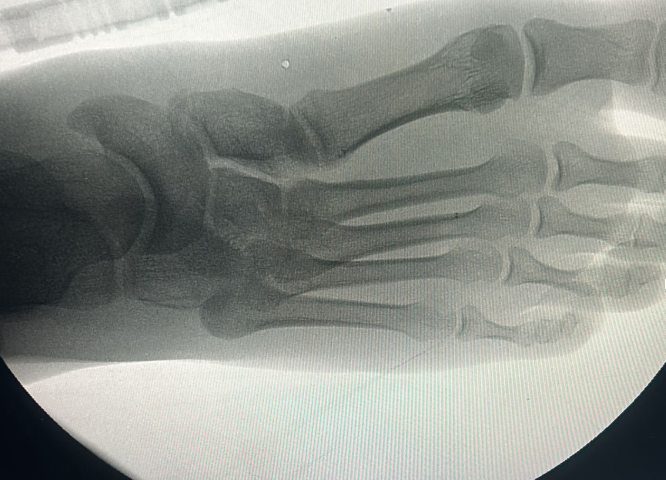

Ayak cerrahisi görseli Ayak cerrahisi görseli 2

• Artroskopik cerrahi: Kapalı yöntemle kıkırdak ve bağ onarımları